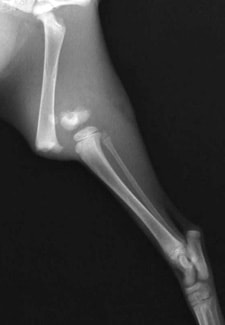

前肢の骨折:橈骨尺骨骨折

![]() 骨折時 |

![]() 手術後 |

![]() 骨折治癒 |

![]() 最後に金属の金具を取り除き完治 |